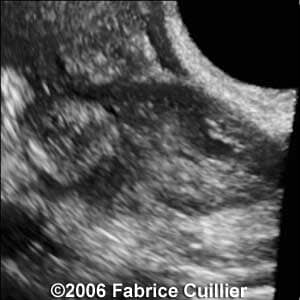

These are some cases of ectopic pregnancy (GEU) using the 2D and 3D scans.